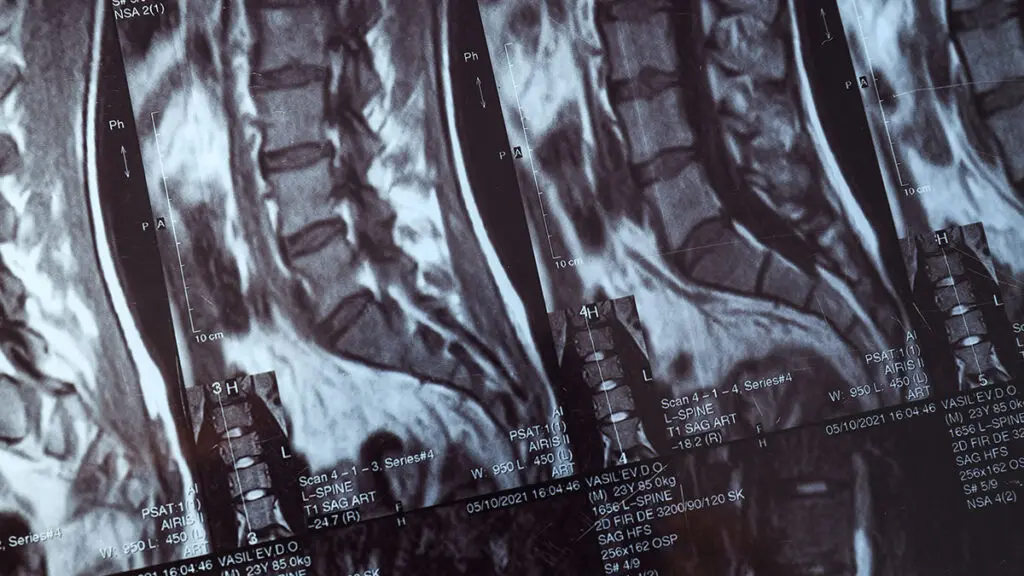

Global Spine Solutions è il centro specialistico a Roma per il trattamento neurochirurgico dei tumori spinali. Il team di neurochirurghi con specializzazione in neurochirurgia oncologica vertebrale esegue interventi di alta complessità per la rimozione di neoformazioni primitive e secondarie del canale vertebrale, con l'obiettivo di ottenere la massima radicalità oncologica preservando al contempo la funzione neurologica.

L'approccio ai tumori spinali adottato da Global Spine Solutions è multidisciplinare: ogni caso viene discusso collegialmente con oncologi, radioterapisti e neuroradiologi per definire il piano terapeutico più completo. La microchirurgia spinale oncologica è supportata dalle più moderne tecnologie intraoperatorie, incluso il monitoraggio neurofisiologico continuo per la protezione delle strutture nervose.